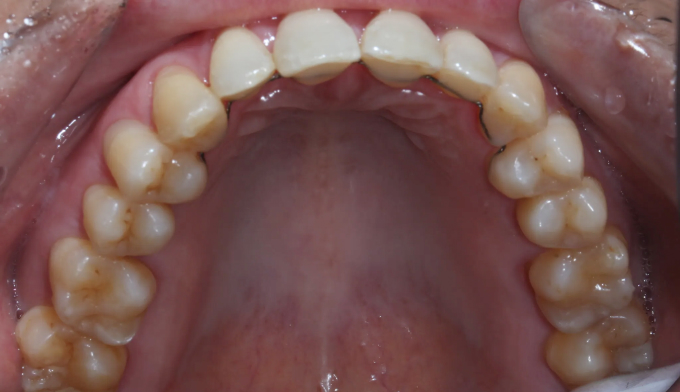

기존에 아래 앞니 사이 공간들에 레진이라는 치아색 나는 재료로 메워놓으셨던 분입니다. 나이가 들면서 잇몸이 약해지게되고 앞니가 점점 더 벌어질 수 있습니다.

타치과에서 다시 레진으로 공간을 없애려고 하였으나 더이상의 보철치료를 원하지 않으셔서, 기존에 존재하던 레진을 제거하면서 동시에 앞니 사이 공간을 교정치료를 이용해 닫아주기로 하였습니다.

기존에 앞니가 벌어지게 된 이유인 치주염을 치료하면서 동시에 앞니 공간을 교정을 통해 닫아줍니다.

총 교정기간은 9개월입니다.